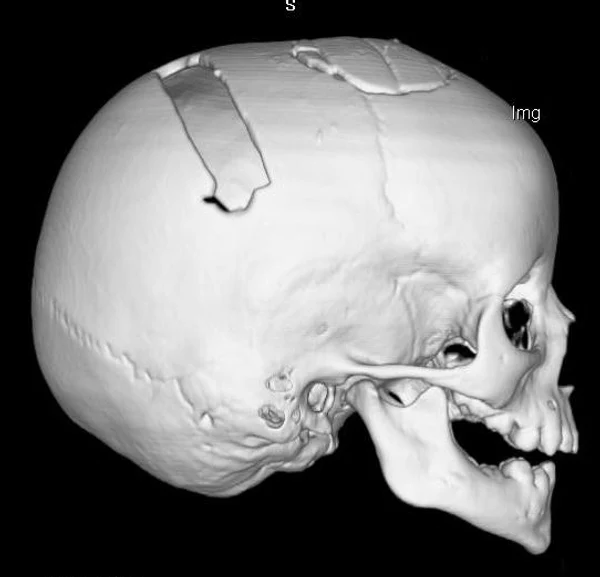

Удаление опухолей черепаВ качестве примера лечения пациентов с опухолями черепа привожу личное наблюдение пациента грудного возраста с опухолью черепа. В возрасте 1 мес. у ребёнка в затылочной области слева родителями обнаружено плотное образование диаметром 5 мм. За 3 мес. до госпитализации образование значительно увеличилось в размерах. При поступлении в возрасте 6 мес. в затылочной области слева (в проекции лямбдовидного шва) имеется безболезненное, плотное, неподвижное, бугристое образование размерами 5 х 4 х 2 см. При КТ и МРТ головы выявлена опухоль черепа в области астериона слева, обладающая преимущественно интракраниальным ростом (рис. 30 а). Ребёнку выполнено удаление опухоли черепа (рис. 30 б). Образовавшийся дефект черепа больших размеров закрыт перфорированной титановой пластиной (рис. 30 в). При наблюдении пациента в течении 2-х лет рецидива заболевания и деформации черепа не отмечалось.